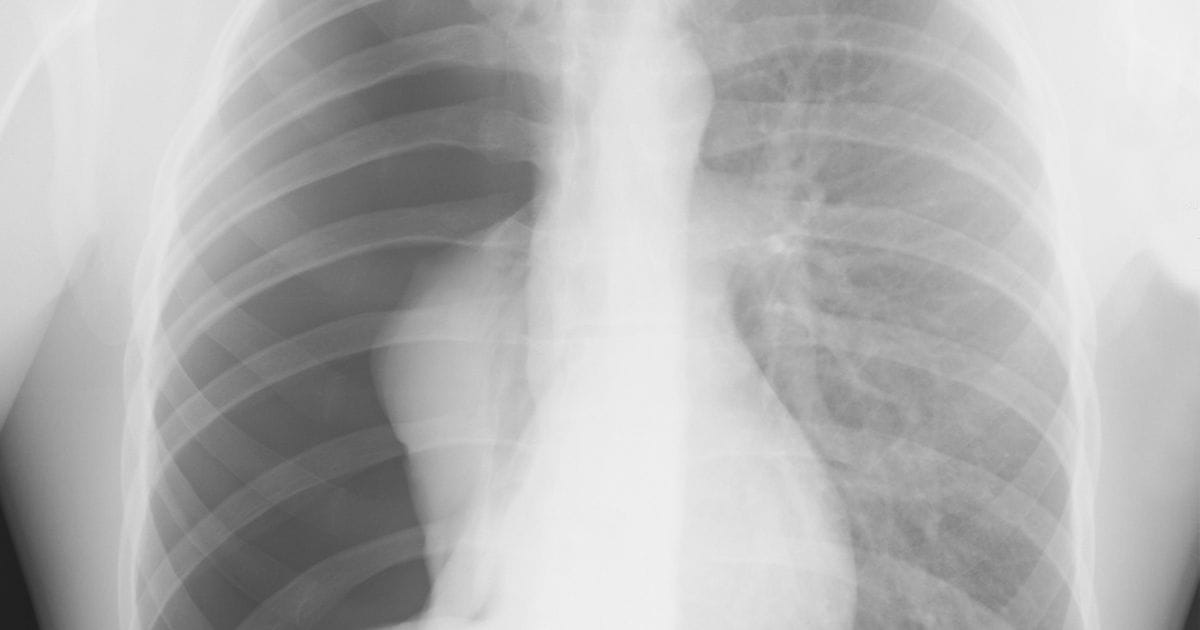

Pneumothorax is also called a collapsed lung. When air enters the pleural cavity (the space between the lung and chest wall), the buildup of air puts pressure on the lung. The pressure decreases the lung’s ability to expand and recoil with inspiration and expiration, resulting in lung collapse. The development of pneumothorax can be life-threatening and may require rapid interventions. This course will discuss traumatic and atraumatic pneumothorax, their signs and symptoms, treatment methods, and chest tube management.